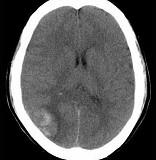

问题 男,37岁,头痛、头晕1年余,加重3天,CT检查如图所示,最可能的诊断为()

选项 A.脑出血 B.脑血管畸形并出血 C.脑膜瘤并出血 D.颅内动脉瘤 E.转移瘤并出血

答案 C